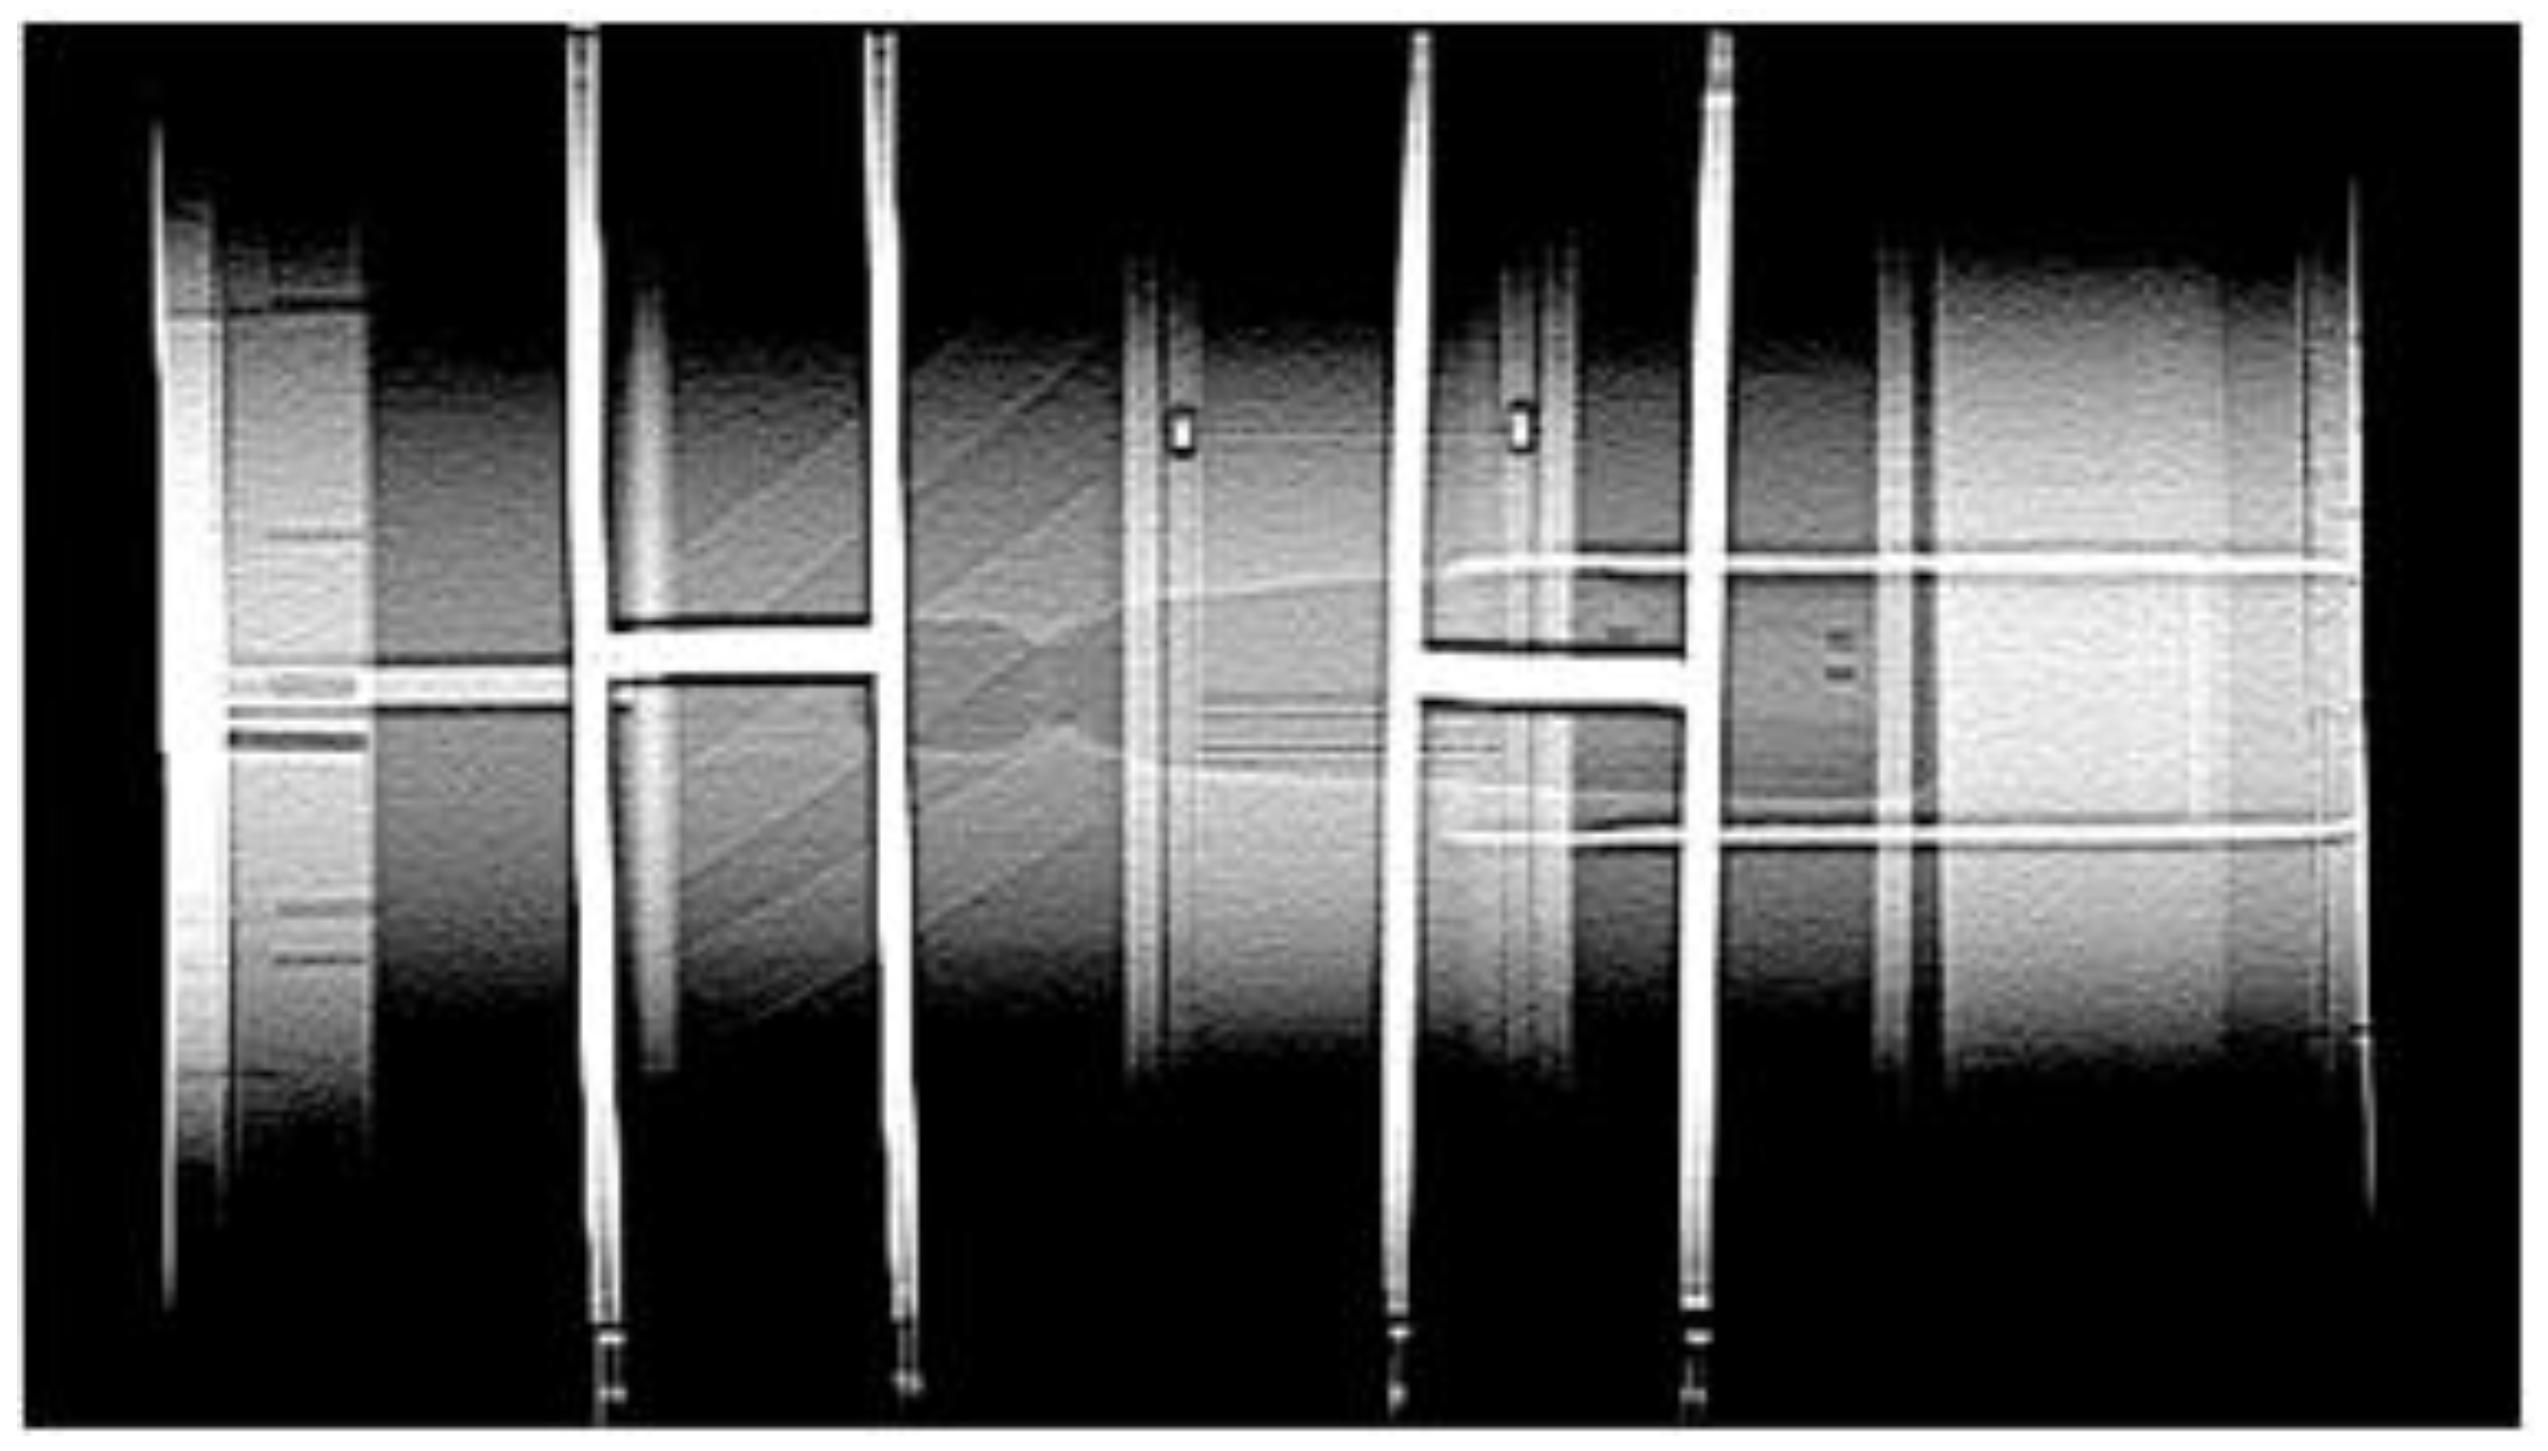

For contrast resolution, the CTA YOLO results are shown in Figure 12. The circles are the objects for detection. The object detection process for the images was conducted in a manner similar to that for the spatial resolution. Phantom evaluation criteria were subsequently applied to the detected images. If any of the circles up to the fifth circle was detected, it was considered a pass. Custom Contrast Resolution Accuracy (CCRA) is expressed as the number of images correctly identified as pass or fail among the images obtained through object detection images (TODI) across the number of total test images. The formula is calculated as follows:

Figure 12. (a) Sample nonpass images of CTA-YOLOv8 applied for contrast resolution; (b) Sample pass images of CTA-YOLOv8 applied for contrast resolution.